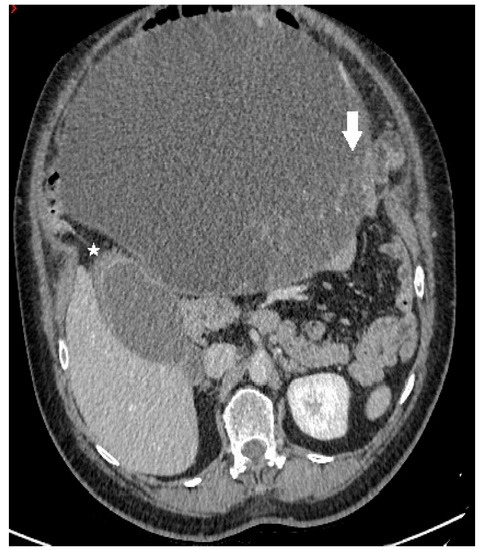

Figure 1.

Axial contrast-enhanced CT image demonstrates a predominantly cystic mass, with enhancing papillary projections (white arrow) arising from the left adnexa (not shown). Notice markedly thickened gallbladder wall with alternating areas of high (white star) and low attenuation, giving a striated appearance with mucosal defect—CT signs of acute gangrenous cholecystitis.